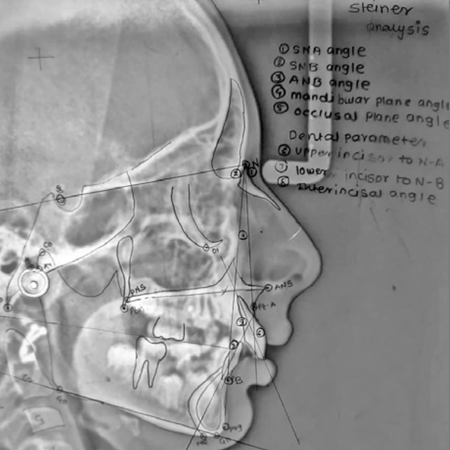

Accuracy of cephalometric landmark identification on artificial intelligence-based software: a comparative study

Introduction: Cephalometry has long been a cornerstone of orthodontic diagnosis and treatment planning. While traditionally performed manually, cephalometric analysis has increasingly shifted toward semi-automated or fully automated computer- based software, due to advances in technology. Objective: This study aims to evaluate and compare the accuracy of anatomical landmarks identified manually by orthodontists using digital tools versus those identified automatically by various artificial...

Precisão da identificação de pontos cefalométricos usando softwares baseados em inteligência artificial: um estudo comparativo

Introdução: A cefalometria tem sido, por muito tempo, um pilar do diagnóstico e do planejamento do tratamento ortodôntico. Embora tradicionalmente realizada de forma manual, a análise cefalométrica tem migrado cada vez mais para softwares computadorizados semiautomatizados ou totalmente automatizados, devido aos avanços tecnológicos. Objetivo: Este estudo teve como objetivo avaliar e comparar a acurácia dos pontos anatômicos identificados manualmente por ortodontistas usando...